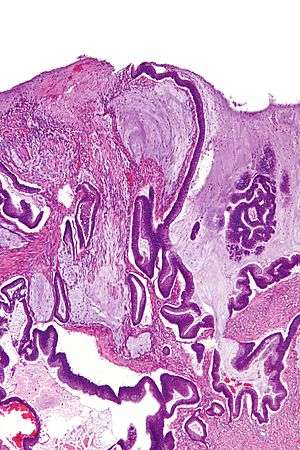

Micrograph of a mucinous adenocarcinoma of the colon. H&E stain.

Mucinous carcinoma is a type of cancer that arises from epithelial cells; these line certain internal organs and skin, and produce mucin (the main component of mucus).